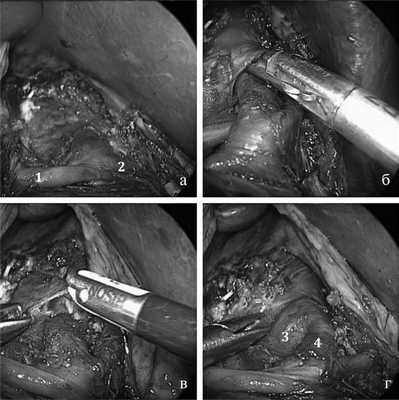

Начиная с 2011 г. методика интраоперационной ультразвуковой допплерографии с целью определения локализации кавернозного отдела внутренней сонной артерии и/или базилярной артерии применялась нами в 51 случае транссфеноидальных операций. Для сканирования операционного поля нами используется комбинированное устройство, основу которого представляет кюретка click line фирмы «Karl Storz» и допплеровский датчик 16 МГц фирмы «Lassamed». Особенностью данного устройства является то, что его рабочая часть подвижна, это позволяет лоцировать сосуды в различных направлениях (рис. 1).

Рис. 1. Комбинированное устройство. а - устройство для определения местоположения интракраниальных артерий в процессе удаления опухолей основания черепа; б - монитор, на котором отображаются данные, полученные в результате сканирования артерий; в - дистальный конец устройства в положении 0°; г - рабочая часть инструмента подвижна и способна сгибаться до 90° (Р - рабочая часть инструмента).